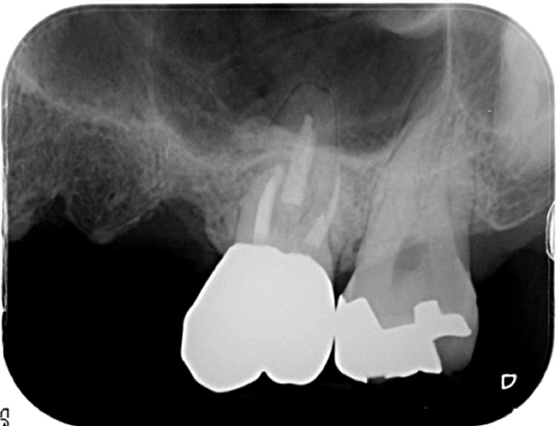

当院の治療成功率が高い理由

精密な治療を行うために利用する機器についてご紹介します。